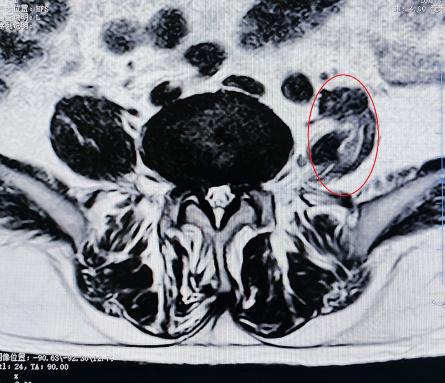

腰椎小關節(jié)增生紊亂:腰椎后方兩側成對的小關節(jié),負責穩(wěn)定脊柱并引導活動。它們如同門上的合頁,一旦因勞損、退變導致軟骨磨損、骨質增生,或發(fā)生微小錯位,就會引發(fā)深層、定位模糊的腰痛。疼痛常在腰部扭轉、后伸時加劇,有時晨起僵硬感明顯。